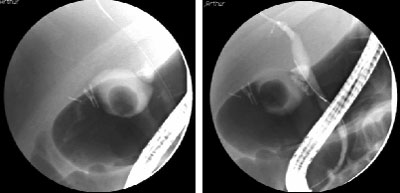

¶νδρας 69 ετών με 3 εντερορραγίες την τελευταία 5ετία. Εικόνα από περιοχή τυφλού.

1. Πρόκειται για αγγειοδυσπλασίες στην περιοχή του τυφλού.